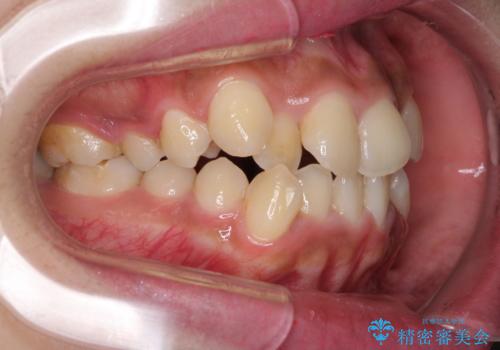

- 八重歯と上下前歯のでこぼこを気にして来院された患者様です。

上下前歯部叢生のスペース獲得のため、上下顎左右小臼歯各1歯(計4本)と全ての親知らずを抜歯して、矯正治療を行うこととしました。